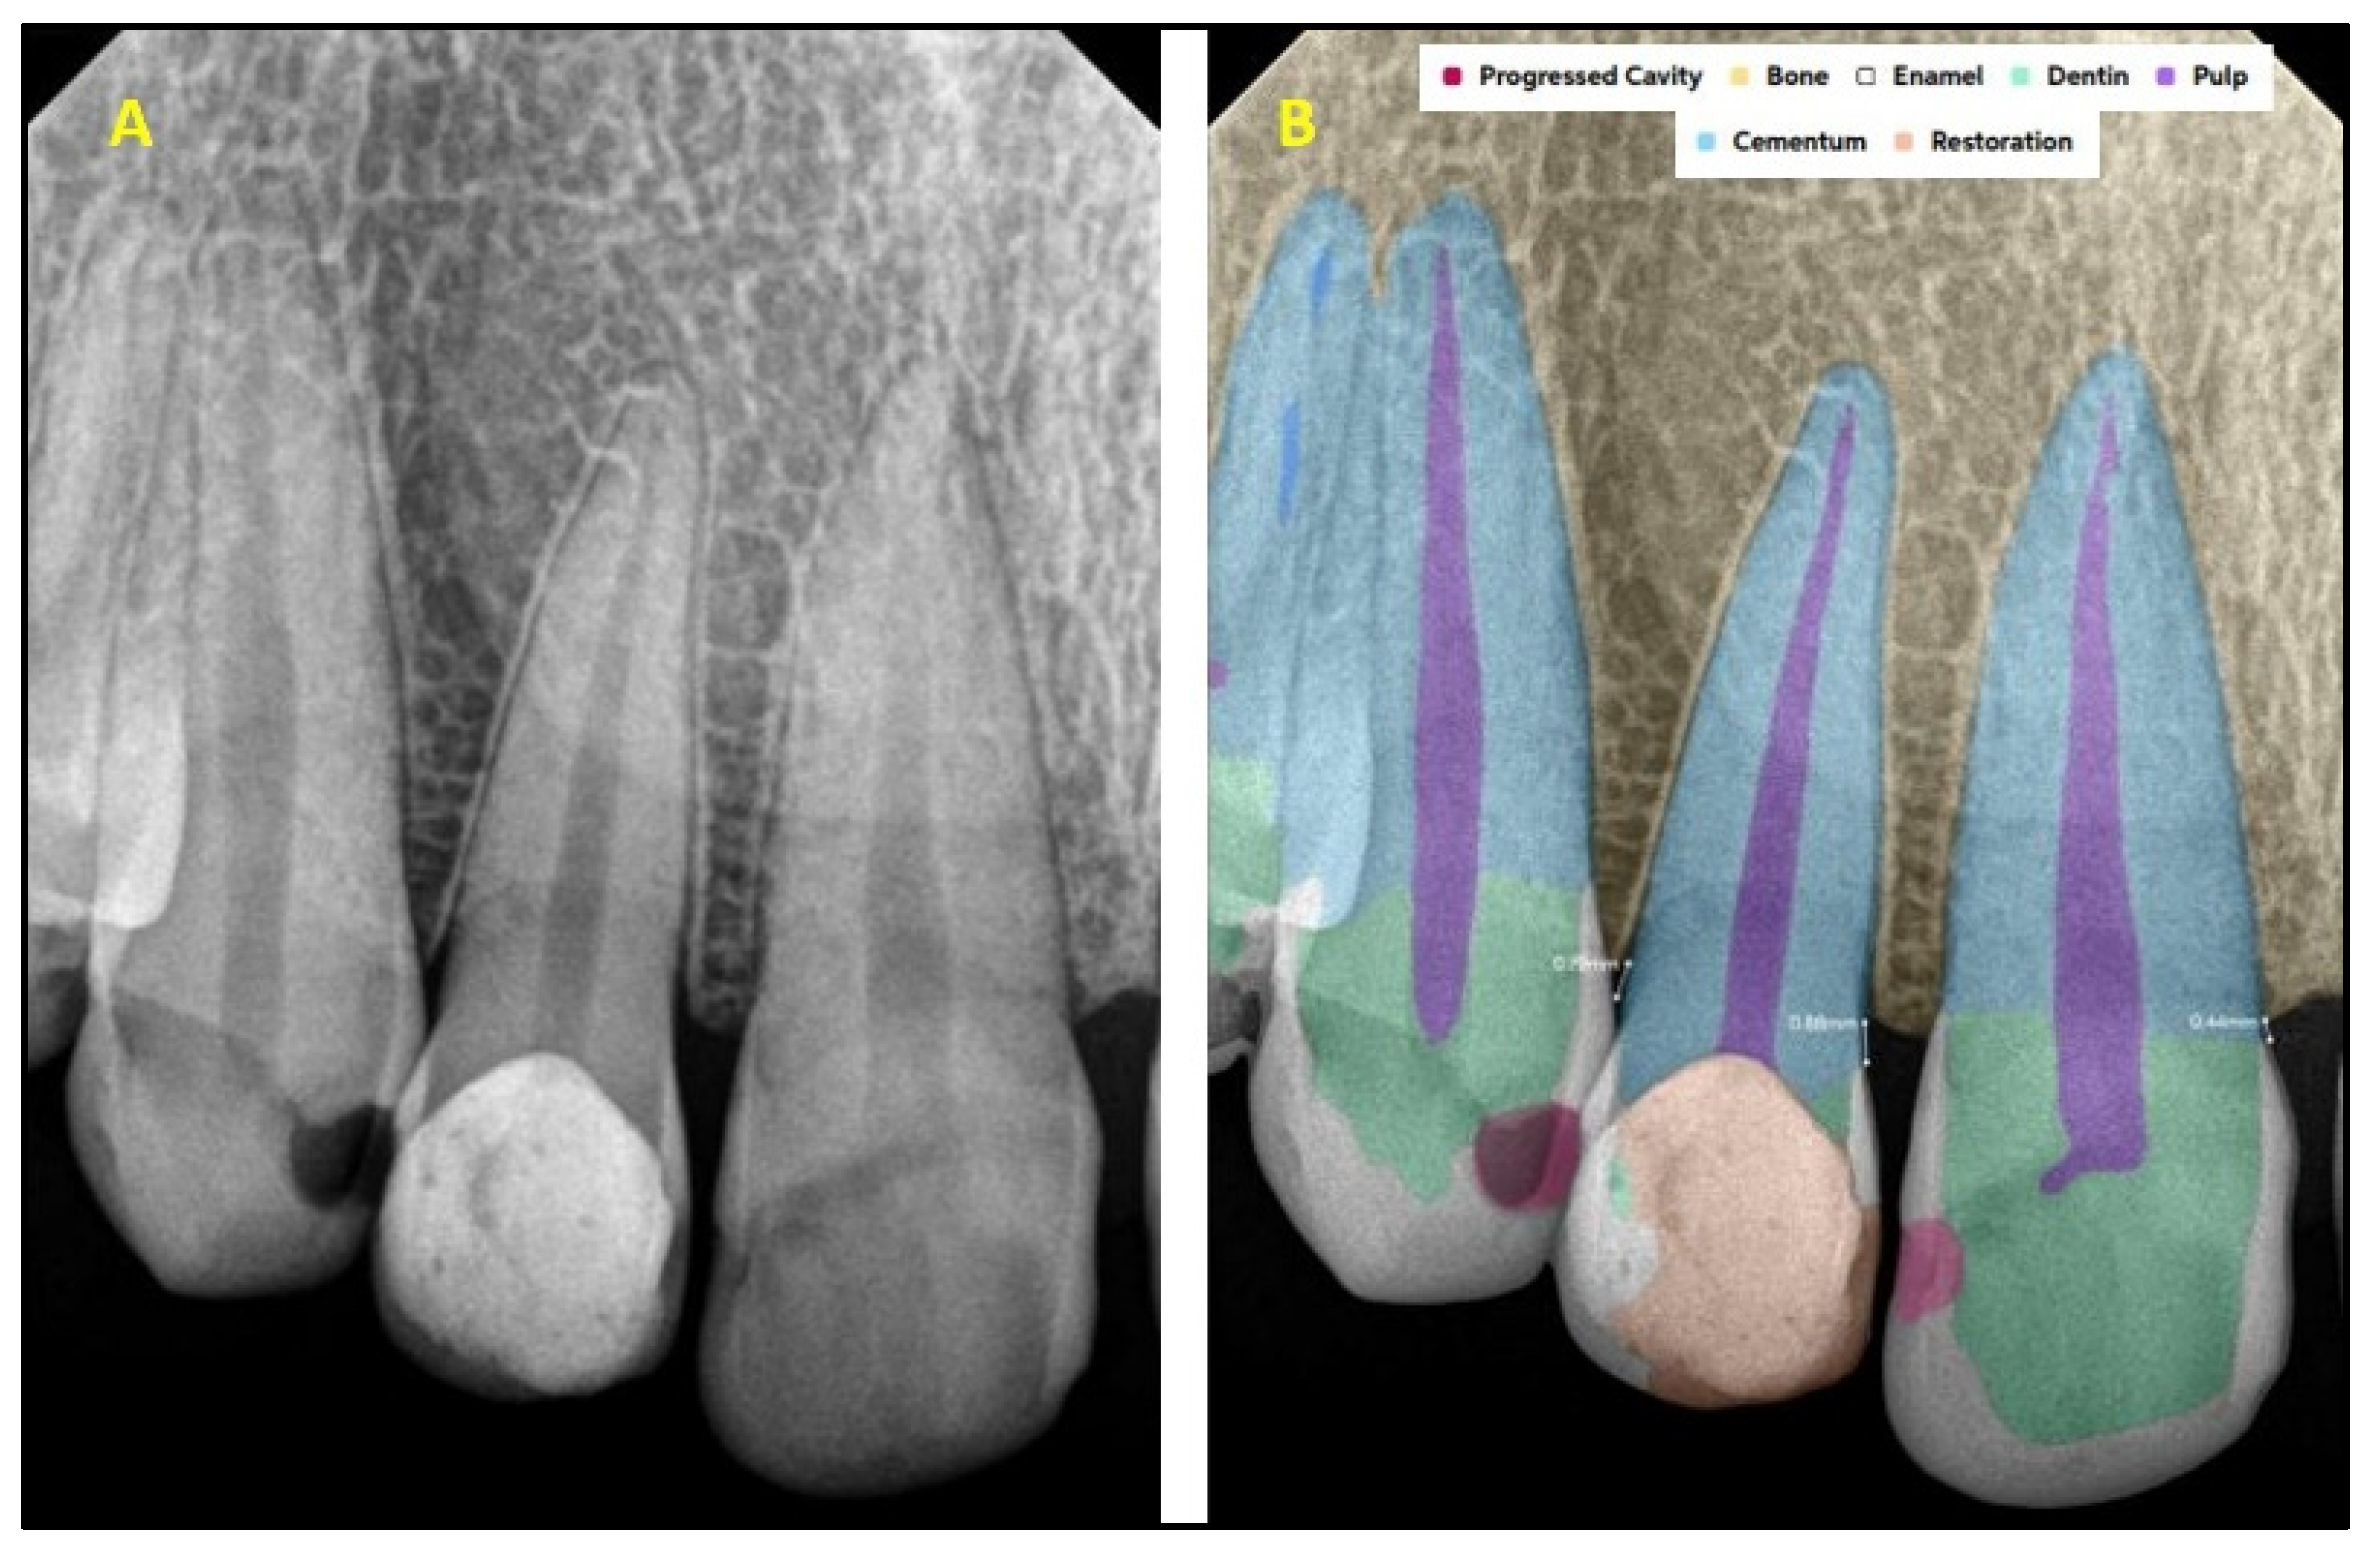

2.2. AI Software Architecture